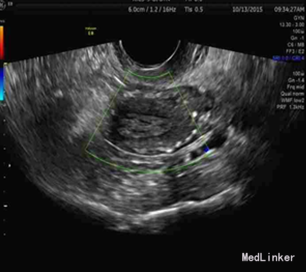

体格检查:T:36.2℃,P:79次/分,R:20次/分,BP:147/72mmHg。 专科检查:外阴萎缩,阴道畅,宫颈轻度糜烂,阴道前壁、宫体大部脱出,后壁少部脱出,子宫及双附件未及异常。 双下肢动静脉彩超:1.双侧颈动脉粥样硬化,2.右侧颈动脉粥样硬化斑块形成,3.双下肢动脉粥样硬化斑块形成,4.右侧肌间静脉血栓形成。盆腔三维:子宫内膜增厚,D-D二聚体定量 1.15 ↑ ug/mL FEU, 血脂全套:总胆固醇 5.65 ↑ mmol/L、低密度脂蛋白 3.75 ↑ mmol/L、载脂蛋白B 1.19 ↑ g/L 、余正常。血管外科会诊建议今日行下腔静脉滤器植入术,降低血栓脱落风险